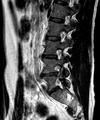

I'm not a qualified radiologist, but I do look at Xrays and scans every day and have done for 35 years. You obviously have a fairly large prolapsed disc at L4-L5, protruding into the foramen, and also compressing the thecal sac.